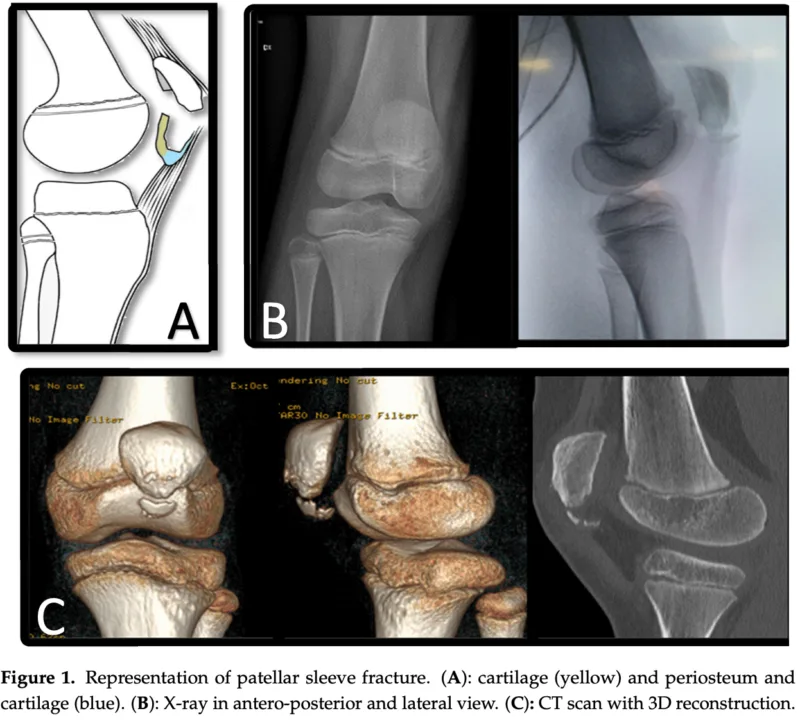

膝蓋骨下極が膝蓋腱に引っ張られることによって, 膝蓋骨本体から軟骨と骨膜が小さな骨片を伴って引き剥がされるように折れる骨折(剥離骨折)です.

引用元:Papotto G. Patellar sleeve fracture: An update of literature. Surgeries 2024. 5.

結果は, sleeve骨折でした.

幸い, 剥がれた骨が小さく, ズレもほとんどなかったので, 手術は行わないで, 運動休止で経過を観察していただくように返事を書きました.

Sleeve骨折は, 膝蓋骨に付着する腱に引っ張られて, 膝蓋骨の一部(骨・骨膜・軟骨)が剥がれるように生じる骨折です. 小児の膝蓋骨に見られる剥離骨折の一種です.

ちなみに“sleeve”とは衣服の袖ではなく, レコード盤を包むジャケットカバーのこと.

膝蓋骨がレコード本体, そこから剥離した骨・軟骨・骨膜がsleeveに相当します.